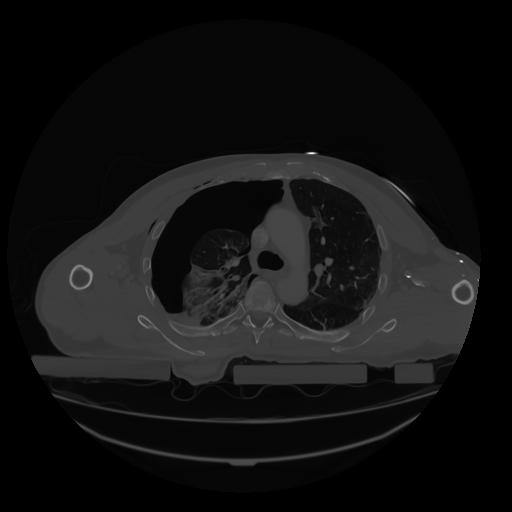

28 CUERPO,CE,Vol,2.0,CUERPO,,